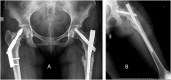

A 27 years old sedentary woman presented bilateral femoral neck stress fractures after having clinically recovered from anorexia nervosa and was treated with bilateral internal fixation.

Conclusion: Although light exercise is usually considered after recovery from anorexia nervosa to improve bone quality, this case of a sedentary patient suggests that weight gain, per se, could increase the stress fracture risk. Because of the physiological and psychological characteristics, these patients should be treated with a multi-disciplinary approach.